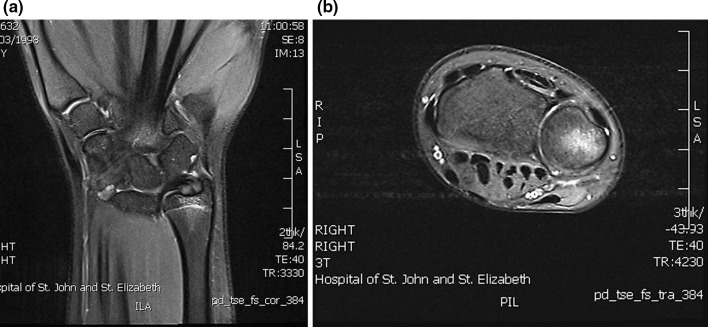

The incidence of paediatric occult fracture was 36.5 % (n = 23). Patients with an occult fracture had an average of 1.5 MRI findings. 26.1 % of patients with fractures had an associated bone contusion, 8.7 % had concomitant injuries to the TFCC (1 sprain, 1 tear), and one patient had an injury to the extrinsic ligaments. Further breakdown and comparison is provided in Table 2. In the paediatric population, the distal radius (Fig. 2) was twice as commonly fractured as the scaphoid (Fig. 3a, b), whilst the scaphoid, lunate, and trapezoid (Fig. 4) were the only carpal bones affected. In comparison, Bergh et al. [13] and Pierre-Jerome et al. [12] report an adult occult fracture incidence of 28 and 23.2 %, respectively, with the former study identifying occult fractures of all carpal bones excluding the pisiform and hamate. These results suggest that occult paediatric wrist fractures are twice as likely to occur in the distal radius as they are in the scaphoid, whereas the incidence of occult fracture is equally spread in both bones in the adult population. Furthermore, the number of carpal bones sustaining occult fractures is limited in children in comparison with adults.

Fig. 3.

a Coronal oblique T1, b coronal oblique PD fat sat: undisplaced transverse fracture line extending through the midpole of the left scaphoid. Associated with pronounced bone marrow oedema and periosteal signal change